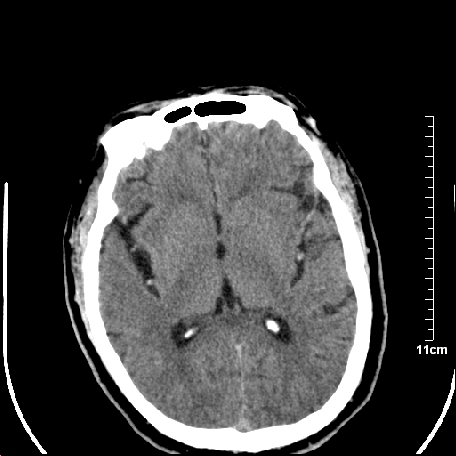

外伤患者,什么病,

外伤患者,没什么症状,

双侧外侧裂,左侧脑沟见高密度结节影,边清,还有鞍上池层面密度也高

都是血管。

脑血管硬化?高血红蛋白症?

高血红蛋白症可能

高血红蛋白症

高血红蛋白血征

1.左额叶脑软化灶。

2.老年脑,基底动脉硬化迂曲。

基底动脉硬化迂曲。高血红蛋白血症。